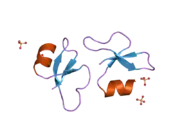

Beta-defensin 1 is a protein that in humans is encoded by the DEFB1 gene.[3][4]

Defensins form a family of microbicidal and cytotoxic peptides made by neutrophils. Members of the defensin family are highly similar in protein sequence. This gene encodes defensin, beta 1, an antimicrobial peptide implicated in the resistance of epithelial surfaces to microbial colonization. This gene maps in close proximity to defensin family member defensin, alpha 1, and has been implicated in the pathogenesis of cystic fibrosis.[4] Single-nucleotide polymorphisms in the DEFB1 gene were associated with plasma kynurenine concentrations in major depressive disorder patients in a genome-wide association study.[5]

- Hoover DM, Chertov O, Lubkowski J (October 2001). "The structure of human beta-defensin-1: new insights into structural properties of beta-defensins". The Journal of Biological Chemistry. 276 (42): 39021–6. doi:10.1074/jbc.M103830200. PMID 11486002.